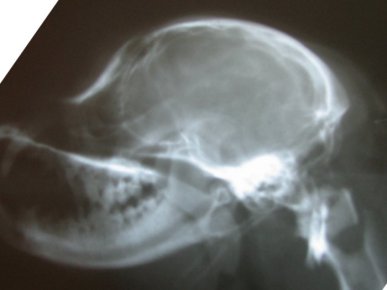

Based on my findings, a study was eventually done to determine

if a skull x-ray could be used to determine amount of CM. The

more CM, the more likely there is to be SM--in most cases. This

study did show there was one skull measurement that did indicate

amount of CM. Here is a comparison of two skull x-rays which

show why this particular measurement indicates amount of CM. The

top one is a skull x-ray of a Cavalier with severe CM (and has

SM as well) and the bottom one is a skull x-ray of a Cavalier

with very little to no CM (and no SM).

The line was drawn from right in front of the 'hole'

(black spot), center of that curved bone (the 'jaw hinge' area)

to where the most thickened area of the skull ends (and the

occipital area begins). In the dog with almost no CM and no SM

you can CLEARLY see there is a lot more lower backskull left

behind/below that line as compared to the dog above--which

literally has almost none! This also happens to be the area

where the cerebellum sits so it would be common sense that the

dog in the top x-ray would have much less room for the

cerebellum than the dog on the bottom--and therefore more CM (chiari

malformation). There just isn't any skull left for there to be

enough room for the cerebellum. It appears here that a good

skull x-ray may be very useful in determining amount of CM and

therefore breeding towards a goal of less and less CM in future

offspring and thereby lessening the prevalence of SM. A skull

x-ray is much cheaper than an MRI which will enable many more

breeders to x-ray for amount of CM in the future as more

information becomes available.